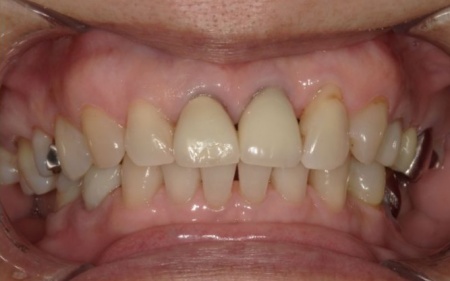

インプラントが顎の骨と結合したあと、人工歯を装着します。

また、手前の歯にも新しい被せ物を装着しました。

最後に、見た目や噛み合わせに問題がないことを確認し、治療を終了しています。